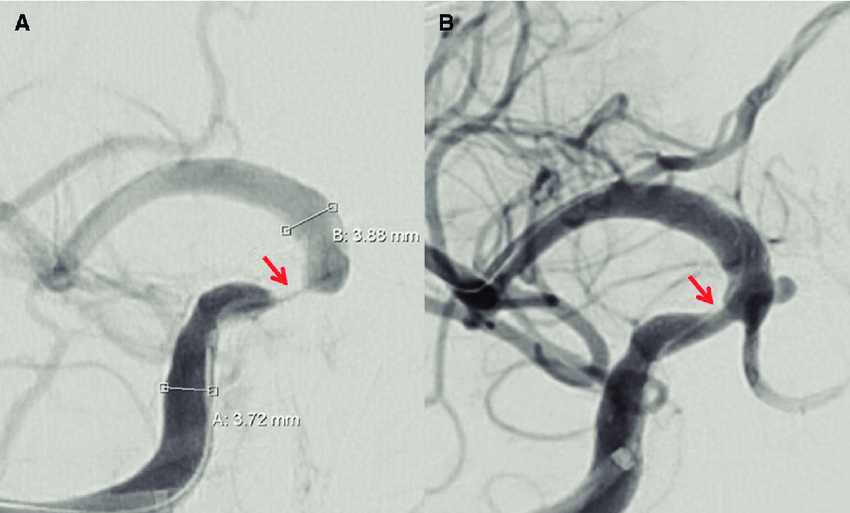

Tratamiento médico vs stent en la estenosis arterial intracraneal grave y sintomática

11 agosto 2022

En los pacientes con accidente isquémico transitorio o accidente cerebrovascular isquémico debido a estenosis aterosclerótica intracraneal grave sintomática, la adición de angioplastia transluminal percutánea y colocación de stent al tratamiento médico, en comparación con el tratamiento médico solo, no produjo diferencias significativas en el riesgo de accidente cerebrovascular o muerte. JAMA, 9 de agosto de 2022.